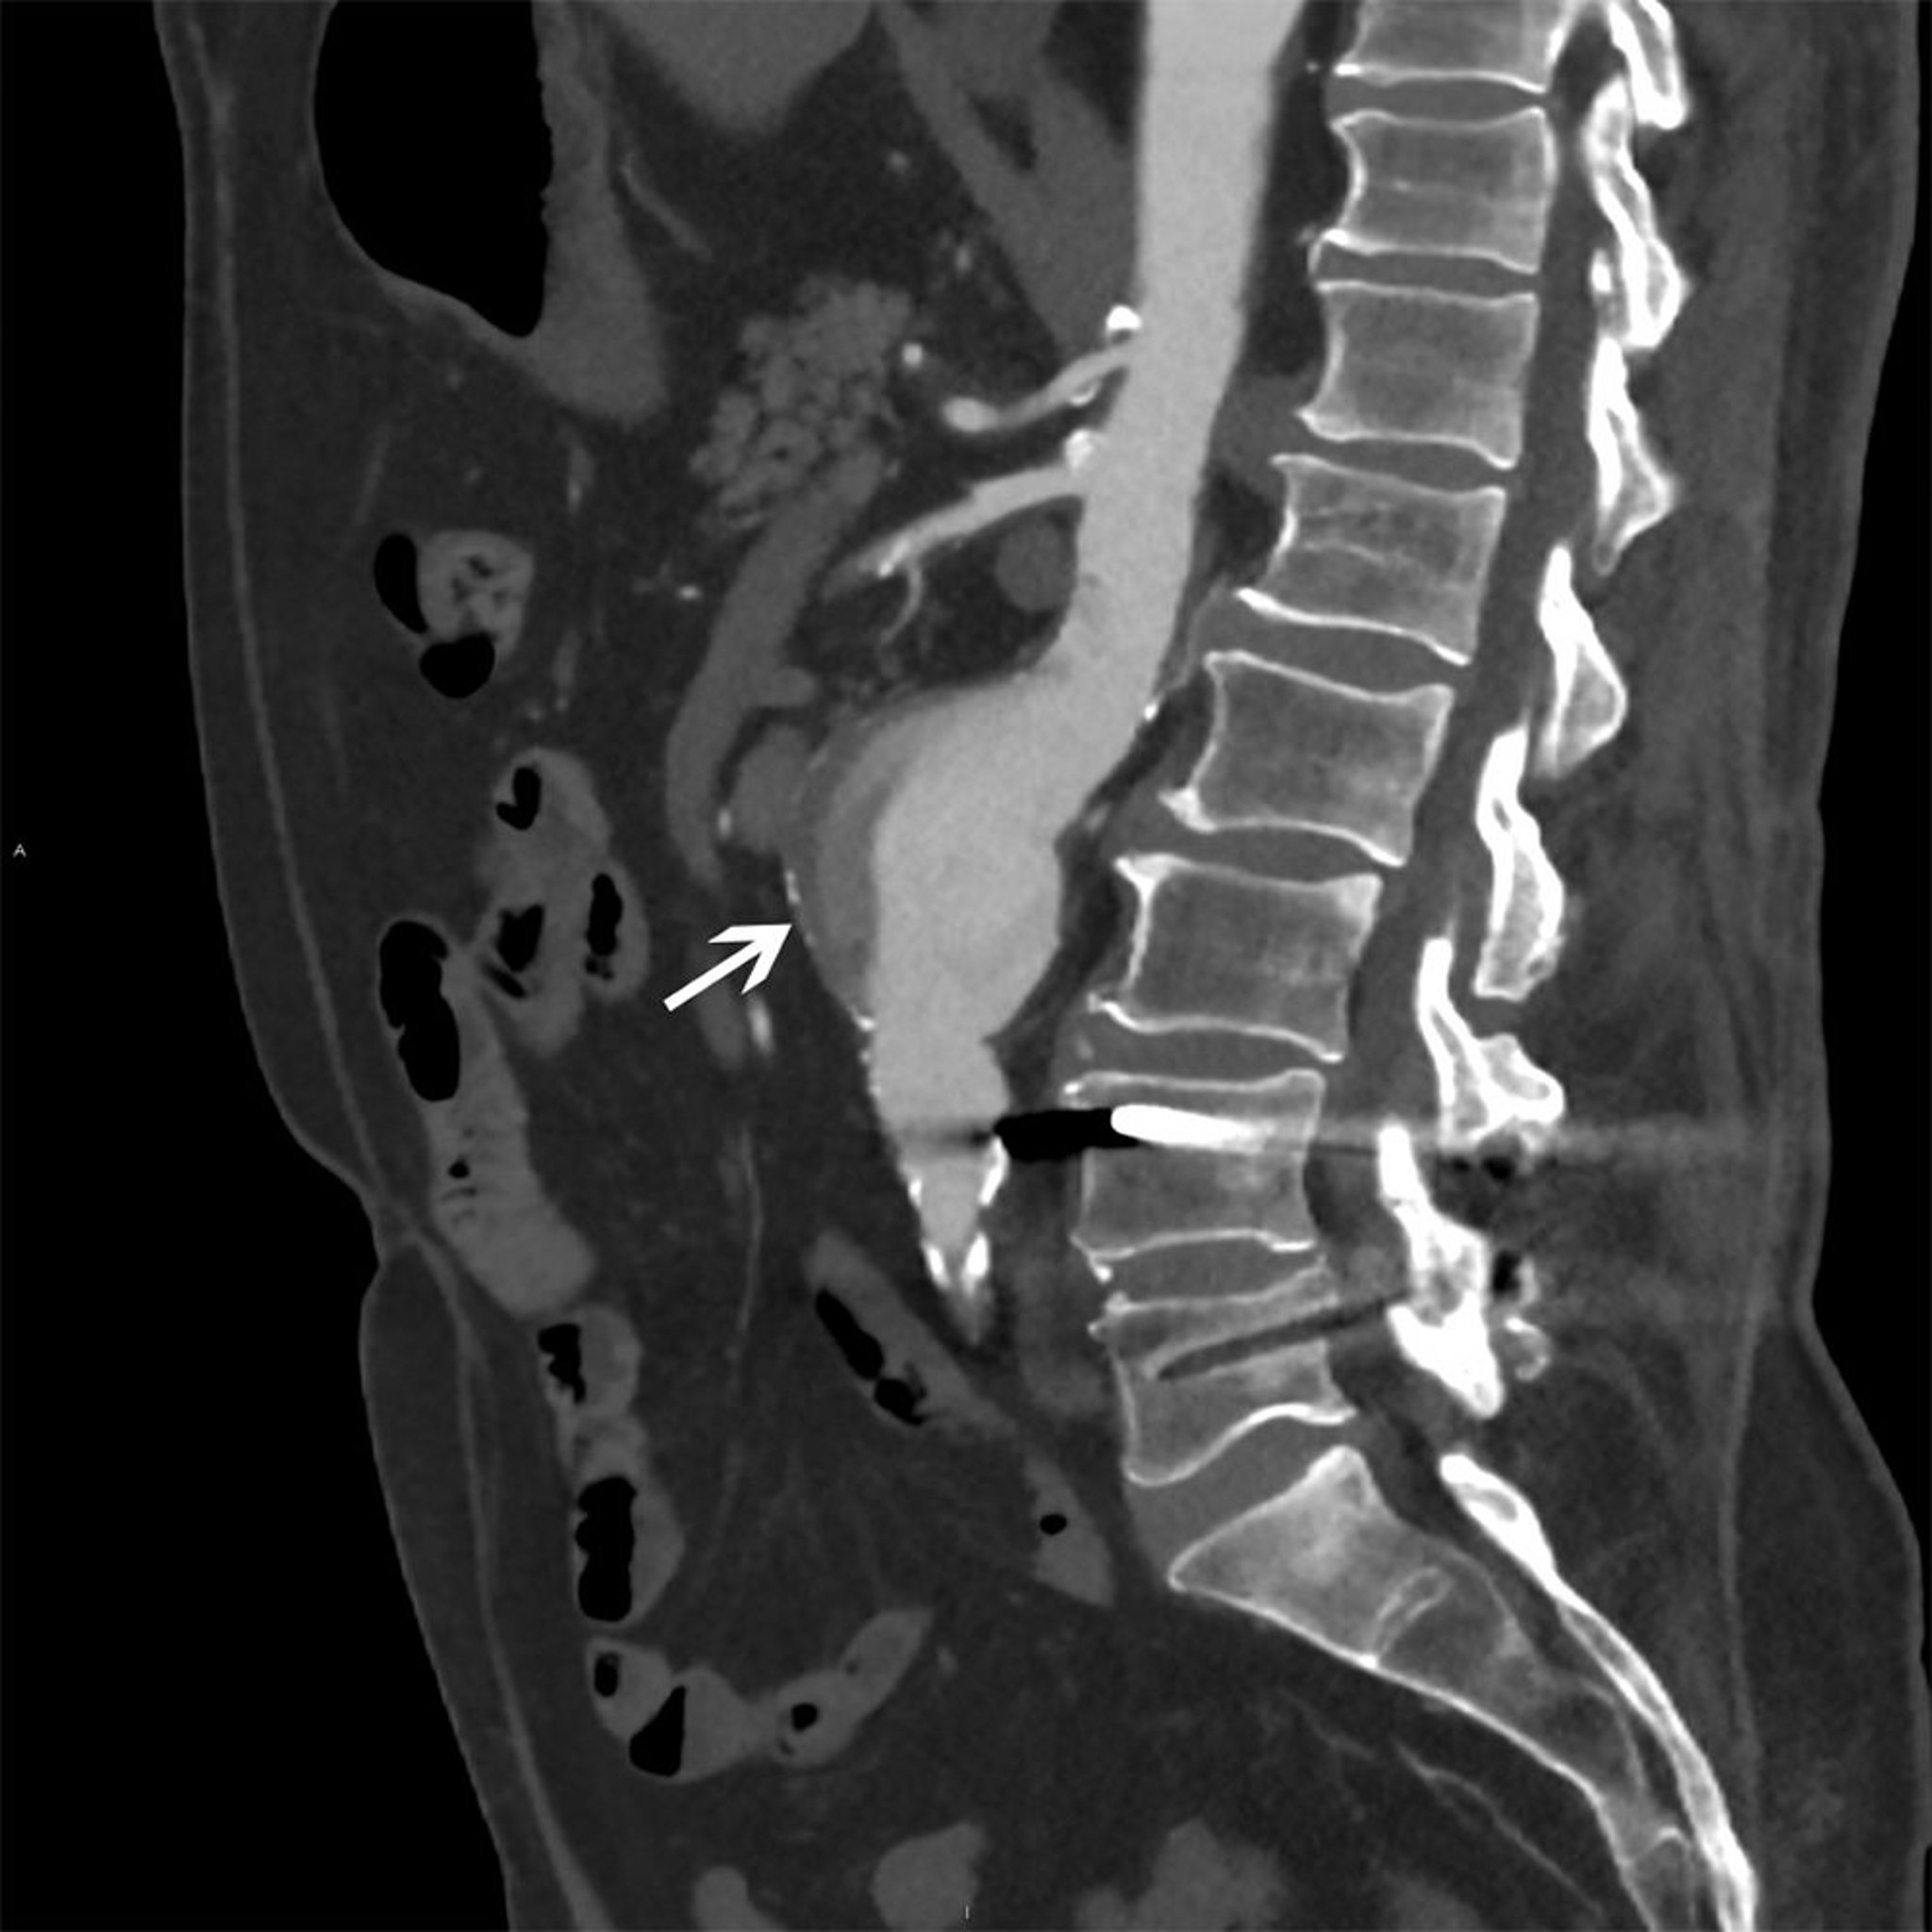

Aneurisma aórtico abdominal (tomografía computarizada)

La flecha blanca muestra un aneurisma aórtico abdominal de 5 cm con flujo heterogéneo y placa mural.